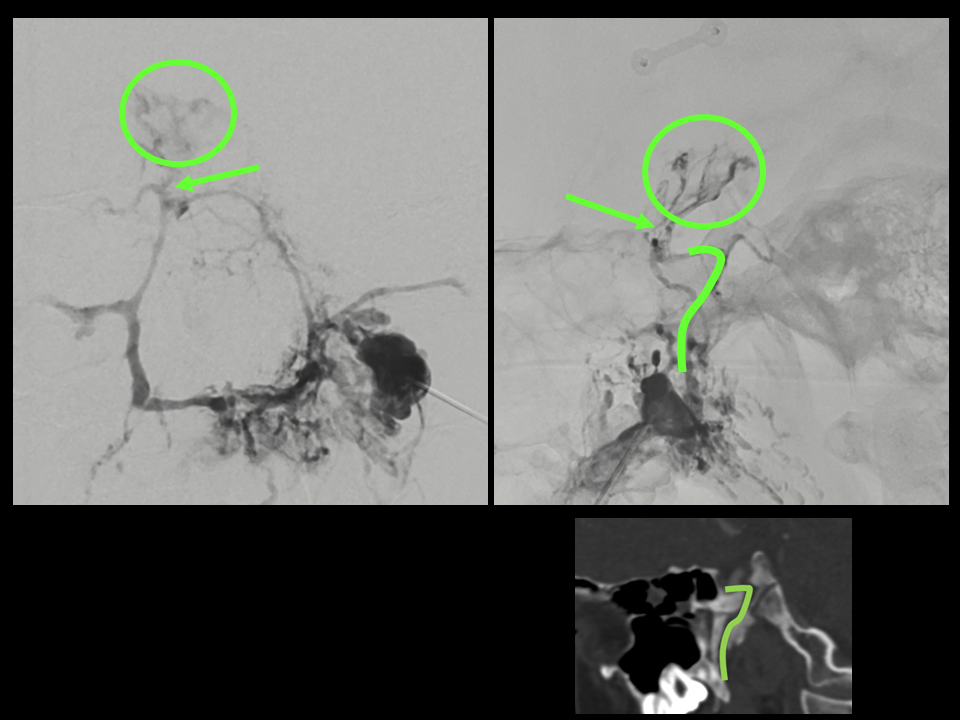

CSF Lymphatic Fistula

A fantastic and unique case